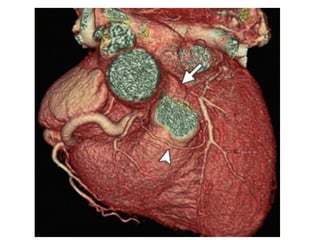

Coronary Aneurysms and Ectasia

Coronary Aneurysms andEctasia • Terminology and Classification • Etiology and pathogeneisis • Examples